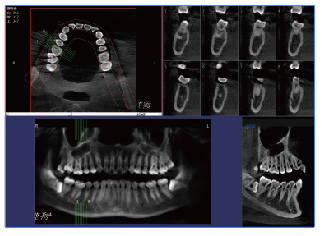

牙齒的健康越來越受到人們的重視,加上飲食因素的影響,往往會導致其患上口腔疾病的幾率增大,因此,一旦出現(xiàn)口腔疾病問題,要做好口腔的檢查,相比傳統(tǒng)的CT檢查,現(xiàn)在的口腔CBCT具備哪些優(yōu)勢?它們兩者之間的對比來看,都分別具備哪些優(yōu)勢?

PLX3000A口腔CBCT—普愛醫(yī)療

一、口腔cbct的優(yōu)勢1、射線劑量低,可廣泛應用于口腔頜面外科,正畸科,正頜外科和種科等。

2、在視野選擇上面,圖像合成等口腔專業(yè)所學個性化的圖像生成方面,口腔cbct的優(yōu)勢更為凸顯,其發(fā)展空間較大。